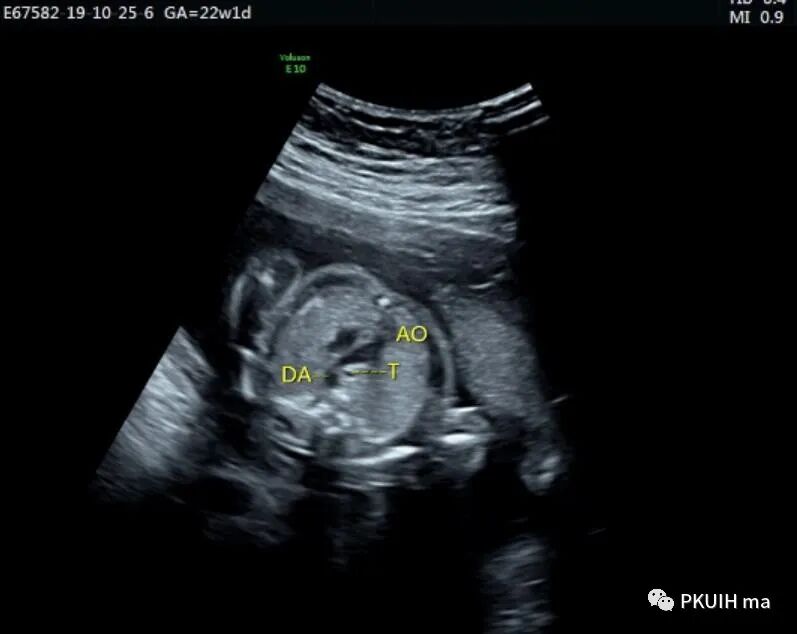

下面几张图都是右位主动脉弓、左动脉导管合并左锁骨下动脉迷走的病例,患儿出生后随访均无明显临床症状

主动脉弓走行于气管的右侧,与左位的动脉导管形成“U”型环(不完全血管环),包绕气管和食管。主动脉冠状切面可见左锁骨下动脉起自于主动脉弓降部,向左肩部走行。